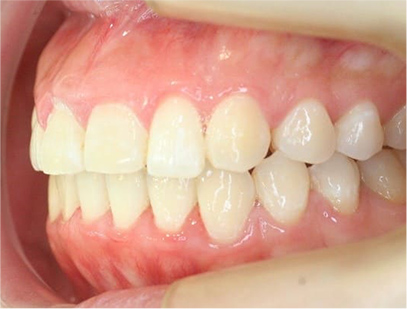

治療後

• 右側

治療前の写真を比べると上下の前歯は綺麗に並び、歯が出ていたことも改善され、 上下の歯はしっかり咬み合っています。 治療期間は、重度の開咬であったために3年弱を必要としました。

• 歯並びが綺麗になり、上下の歯が咬み合った事。

• 上の前歯が出ていたことが改善された事。